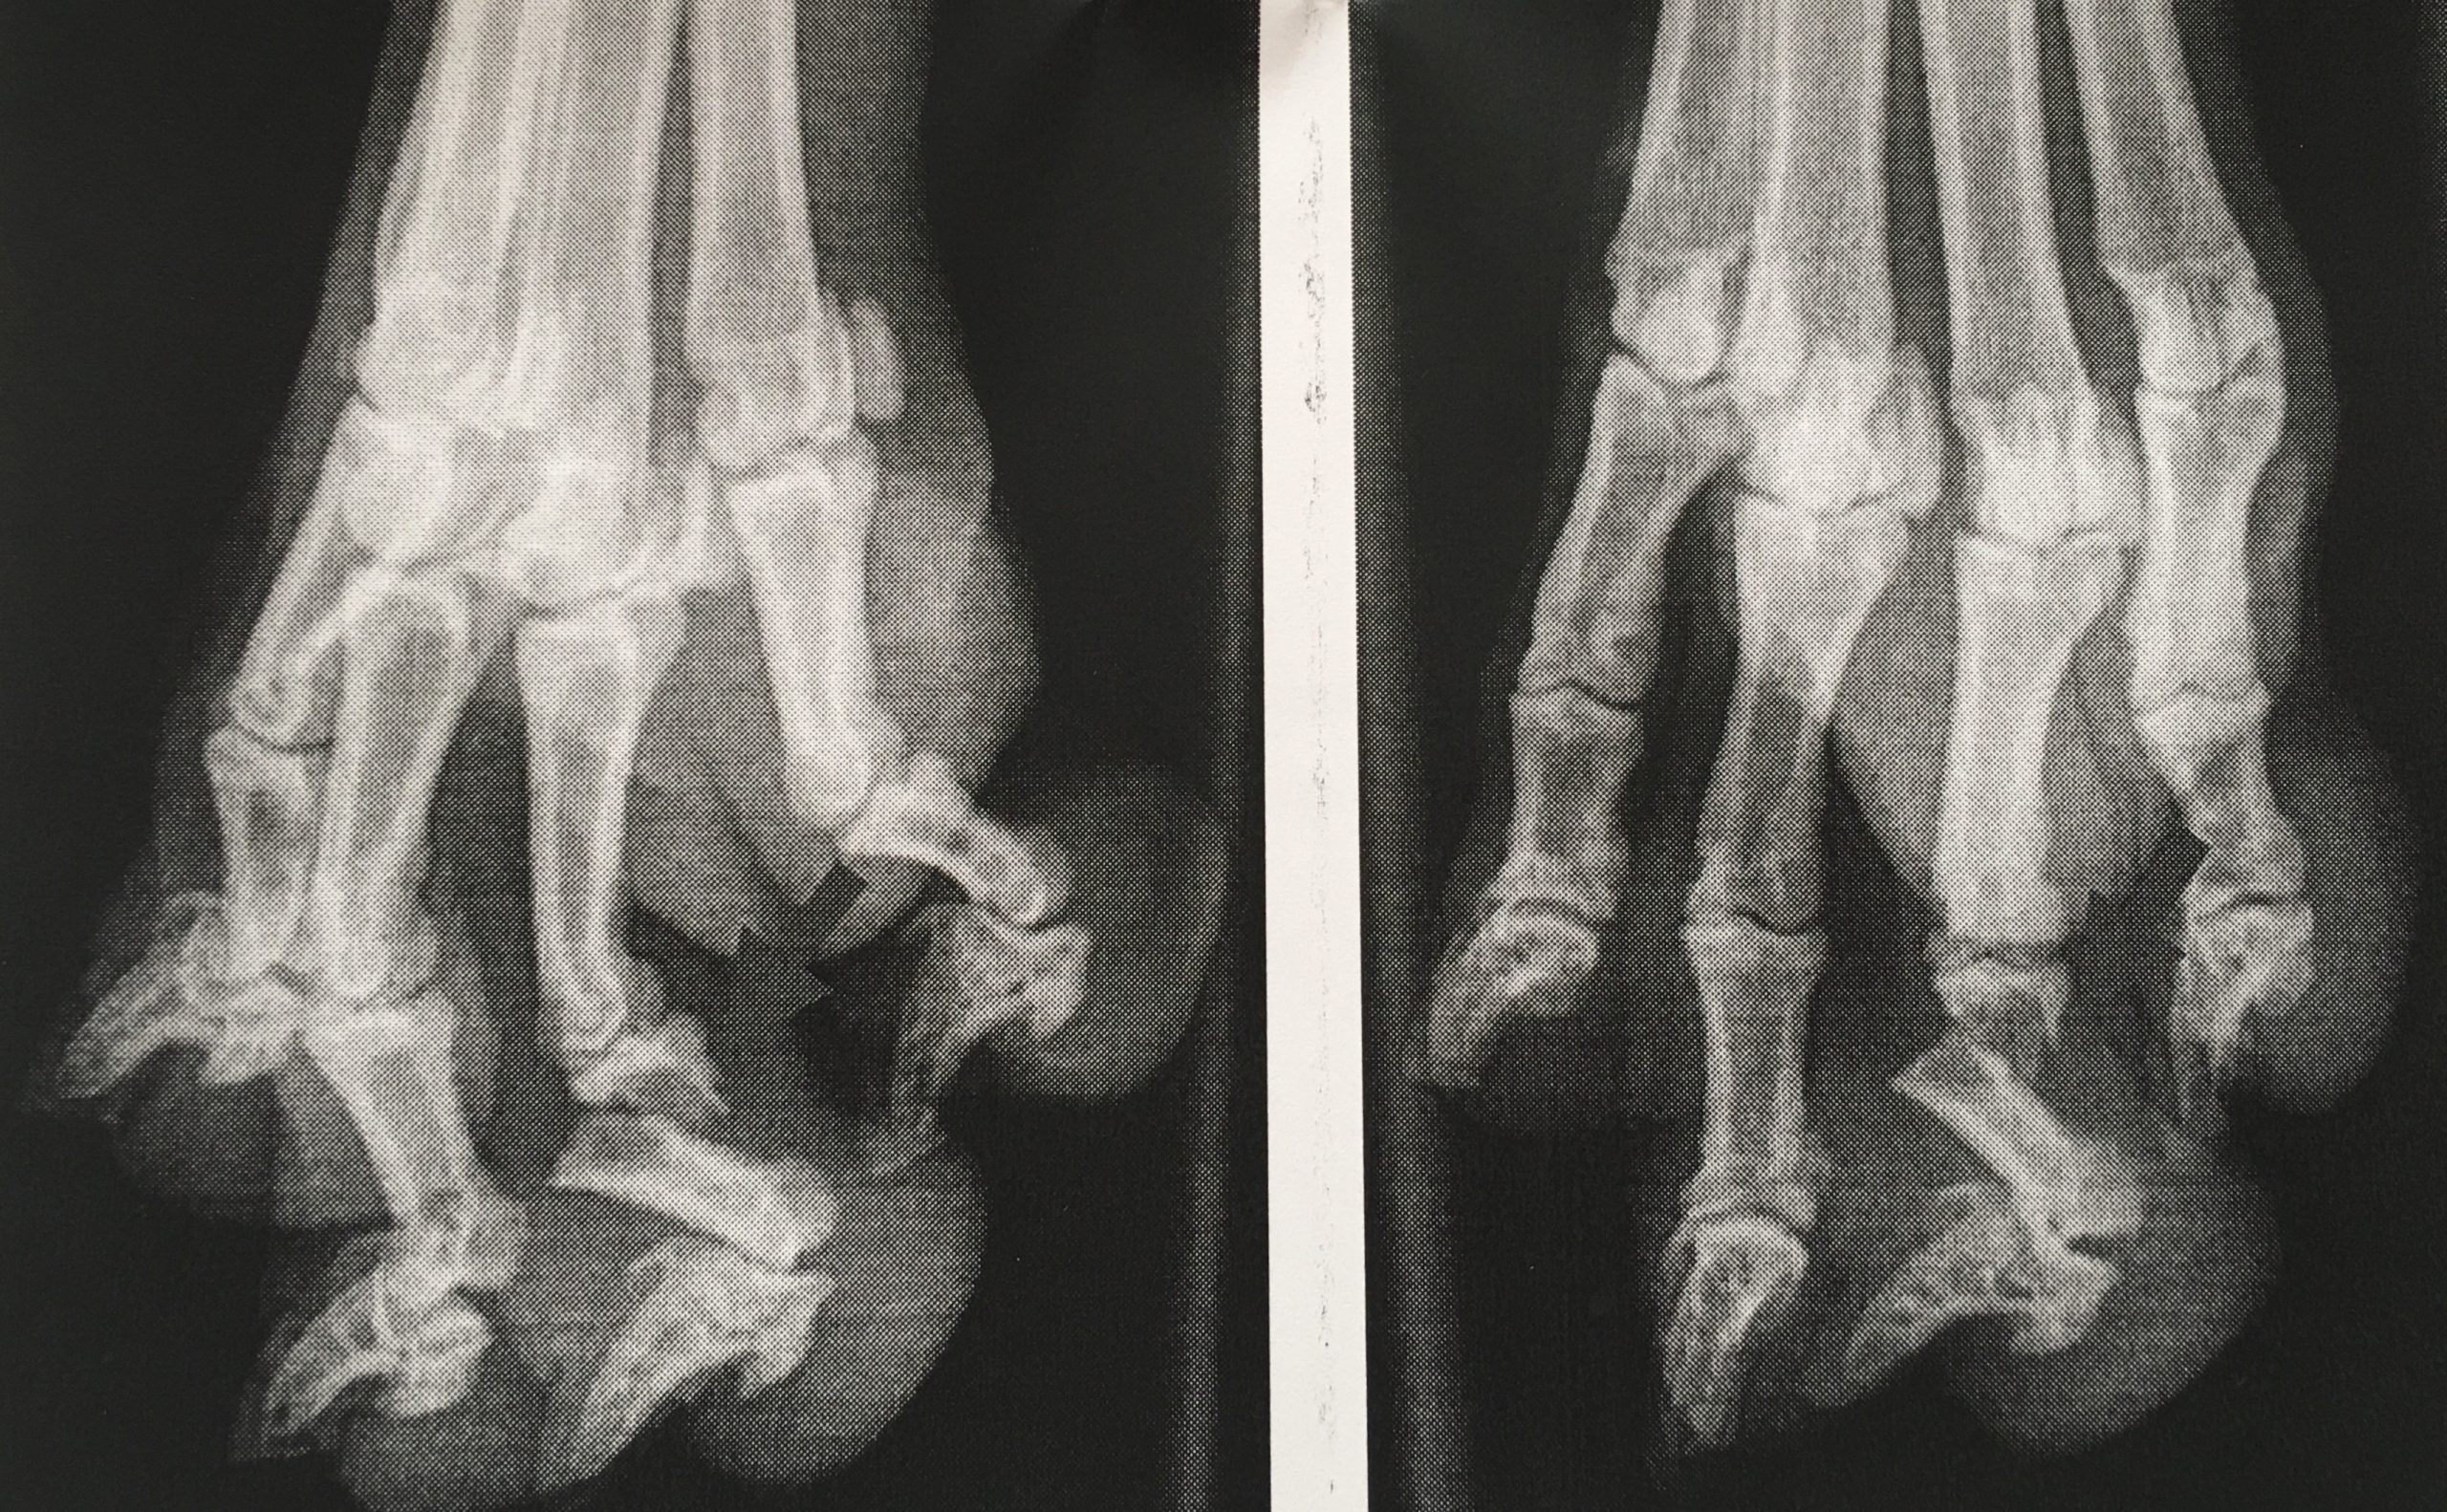

Broke something

Even running around in the garden is too dangerous! Look at at my paws!